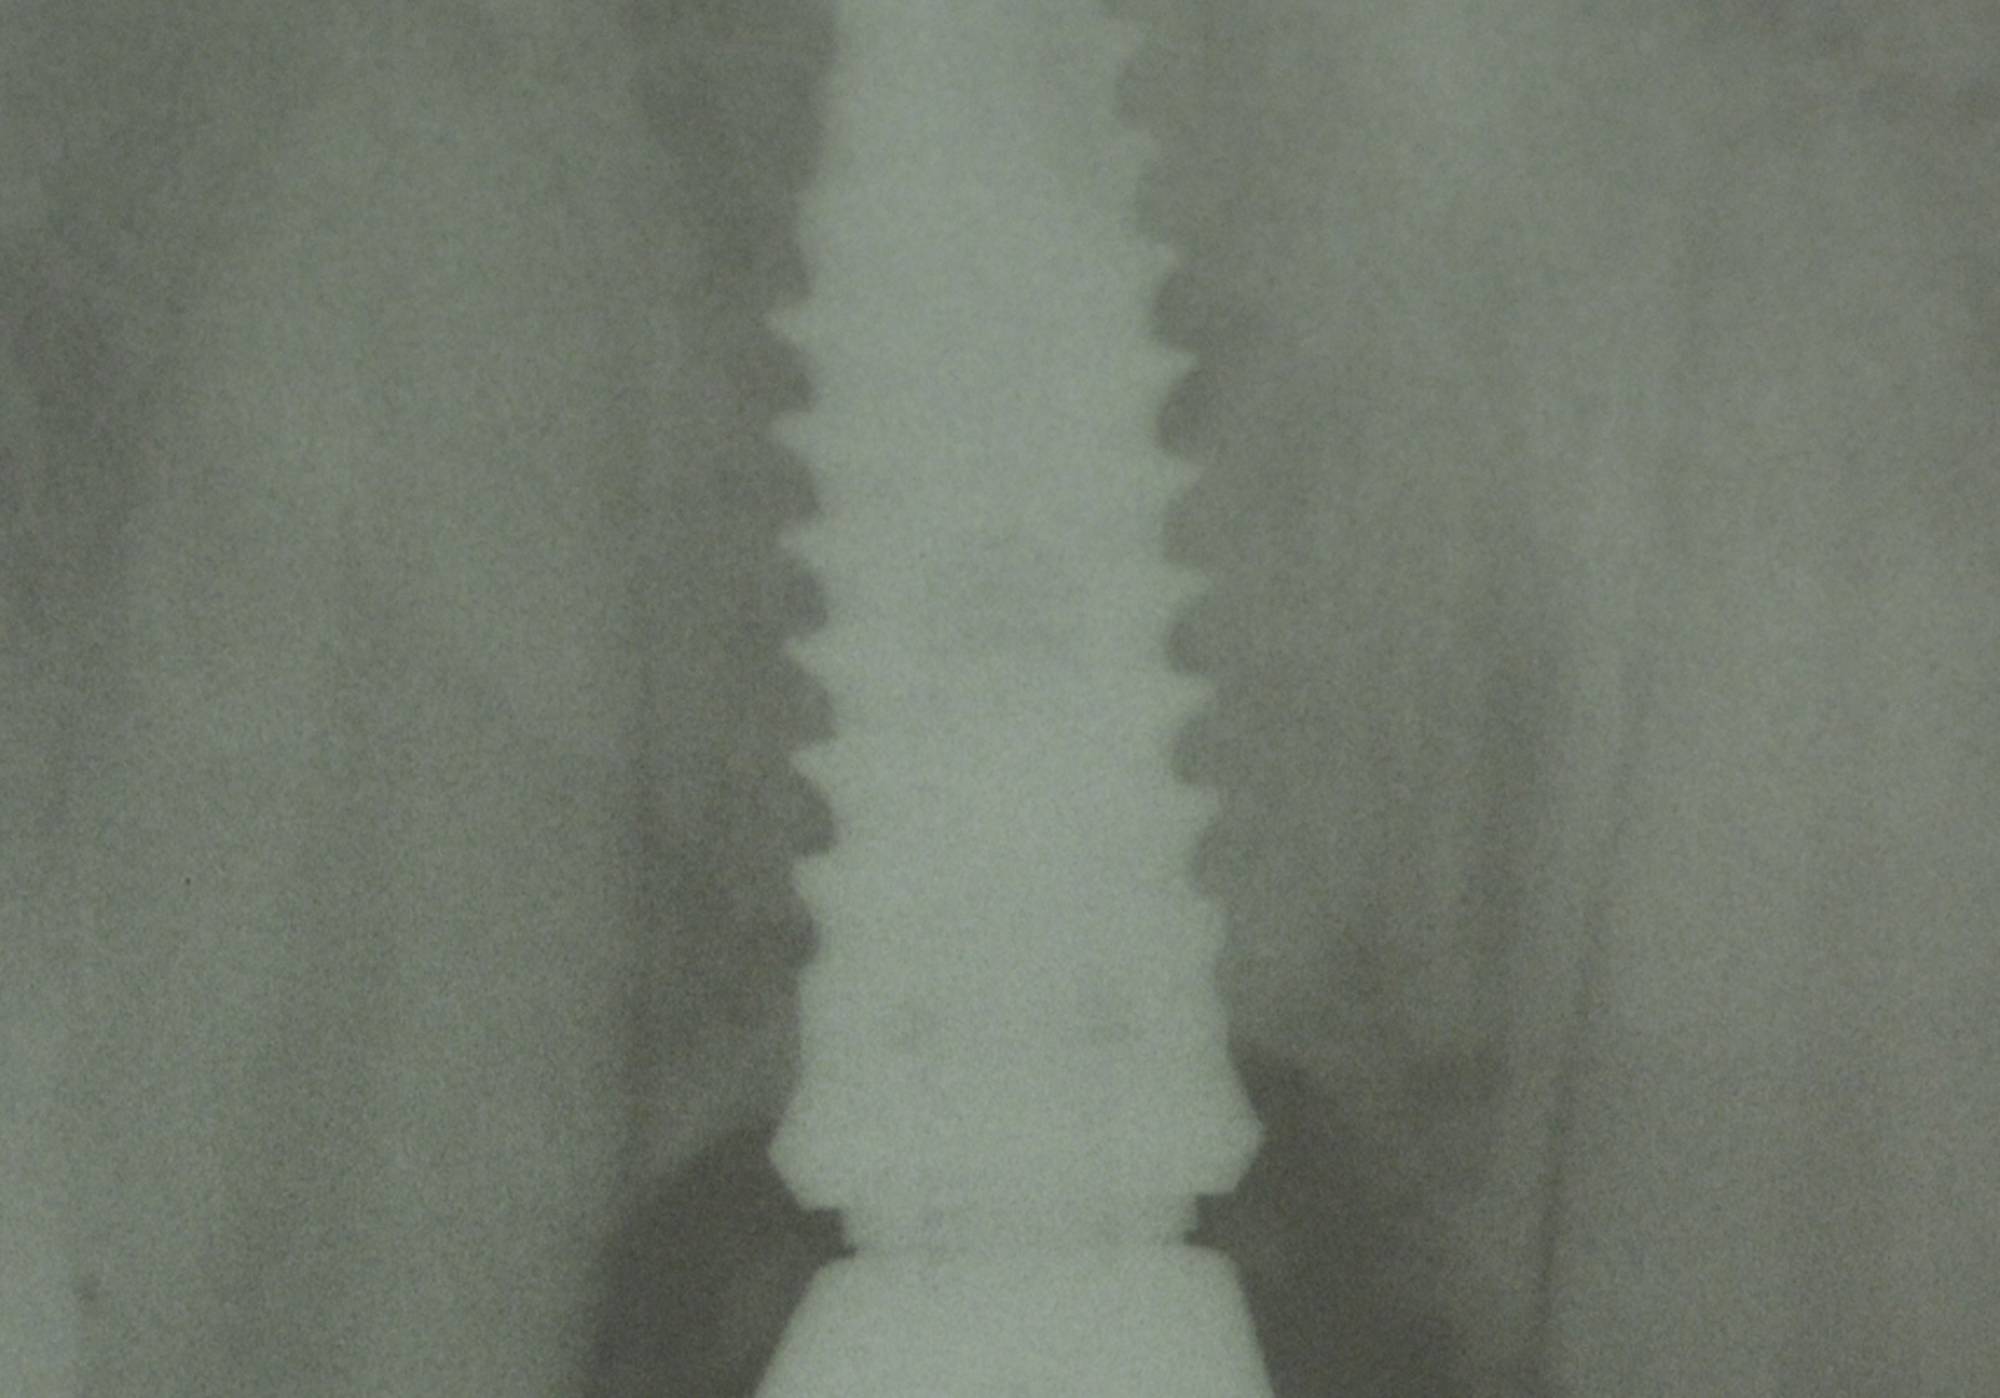

Generalmente devono trascorrere alcuni mesi tra l’intervento chirurgico di inserimento di un impianto e la realizzazione della protesi da fissare ad esso.

In questo lasso di tempo, nel quale l'impianto è sommerso sotto la gengiva e si avvia il processo di guarigione ossea, si realizza l'osteointegrazione, ovvero un intimo contatto fra l’osso e la superficie biocompatibile in titanio dell’impianto.

Tuttavia, in alcuni casi selezionati, è possibile protesizzare gli impianti subito dopo il loro posizionamento, nel giro di pochi giorni o addirittura nel corso della stessa seduta: questa tecnica è definita “carico immediato” e consente al paziente di entrare in Studio con la sua vecchia dentiera e di uscire il giorno stesso con una protesi fissa.